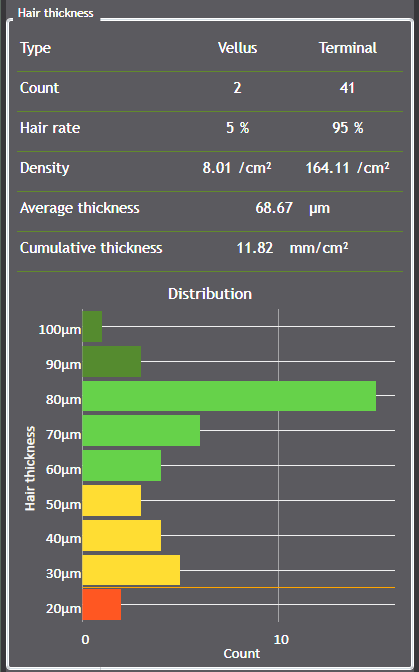

100% automated hair analysis using AI segmentation

Thanks to advanced AI-powered segmentation algorithms, the C-Cube now enables fully automated detection of hair fibers in the image.

Each hair is individually identified, which allows for:

-

automatic diameter calculation,

-

measuring hair length and regrowth,

-

quantification of density.

This automation reduces analysis time, minimizes operator variability, and ensures optimal reproducibility in longitudinal studies.